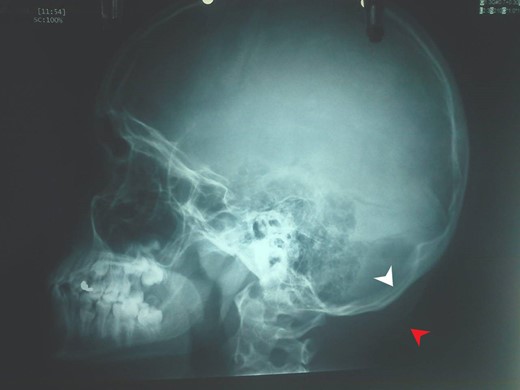

Α 12-year-old girl presented to us with a painless tumefaction on the right suboccipital region evolving for 5 months. Clinical examination did not reveal any other important symptoms or signs. Various explorations carried out, in particular, X-rays (Fig. 1), CT scan with intravenous contrast medium (Figs 2 and 3) and imagery by magnetic resonance with intravenous paramagnetic contrast.

Head profile X-ray. Bone thinning (white arrow) caused by the mass (red arrow).

The CT scan showed that there was only thinning of the bone without erosion or intracranial extension of the mass. There were no signs of calcification, and there was a mild and inhomogeneous uptake of the contrast.